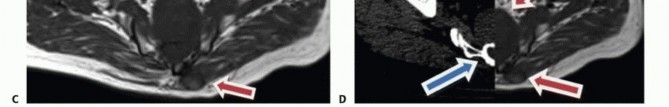

التصوير المقطعي المحوسب والرنين المغناطيسي

- التصوير المقطعي المحوسب (CT): يُعد بتقنية التباين الوريدي الأسلوب الأمثل لتقييم مدى انتشار الورم في العظم وتدميره، والتكلسات المحتملة، والموقع التشريحي، والإمداد الدموي، وعلاقة الورم بالأعضاء الحشوية. يساعد في التفريق بين الأورام الحميدة والخبيثة.

- التصوير بالرنين المغناطيسي (MRI): بتقنية التباين، يُعد حاسمًا لتصوير الأنسجة الرخوة ومدى انتشار الورم فيها، وعلاقته بالأنسجة المحيطة (مثل الأوعية الدموية والأعصاب والعضلات والأعضاء الحشوية). يُعتبر الأسلوب الأمثل لتصوير الأنسجة الرخوة نظرًا لقدرته الفائقة على التمييز مقارنةً بالتصوير المقطعي.